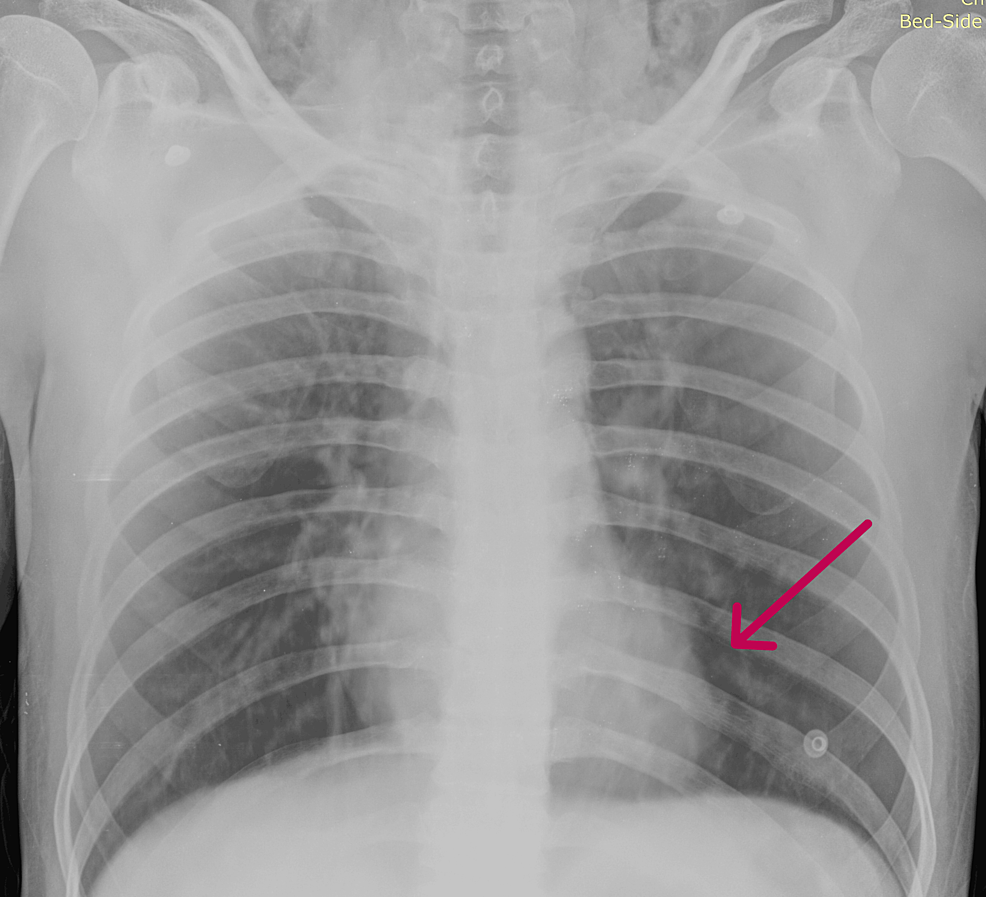

A Chest Radiograph showed a small air pocket in the paraspinal space Air Pocket After Surgery Surgical emphysema is another term for subcutaneous emphysema. Subcutaneous emphysema (sce, se) occurs when gas or air accumulates and seeps under the skin, where normally no gas should be present. Pneumomediastinum is usually caused by air moving into your mediastinum from an injury to an internal organ or structure. It occurs when air or gas enters the subcutaneous tissue, which. Air Pocket After Surgery.